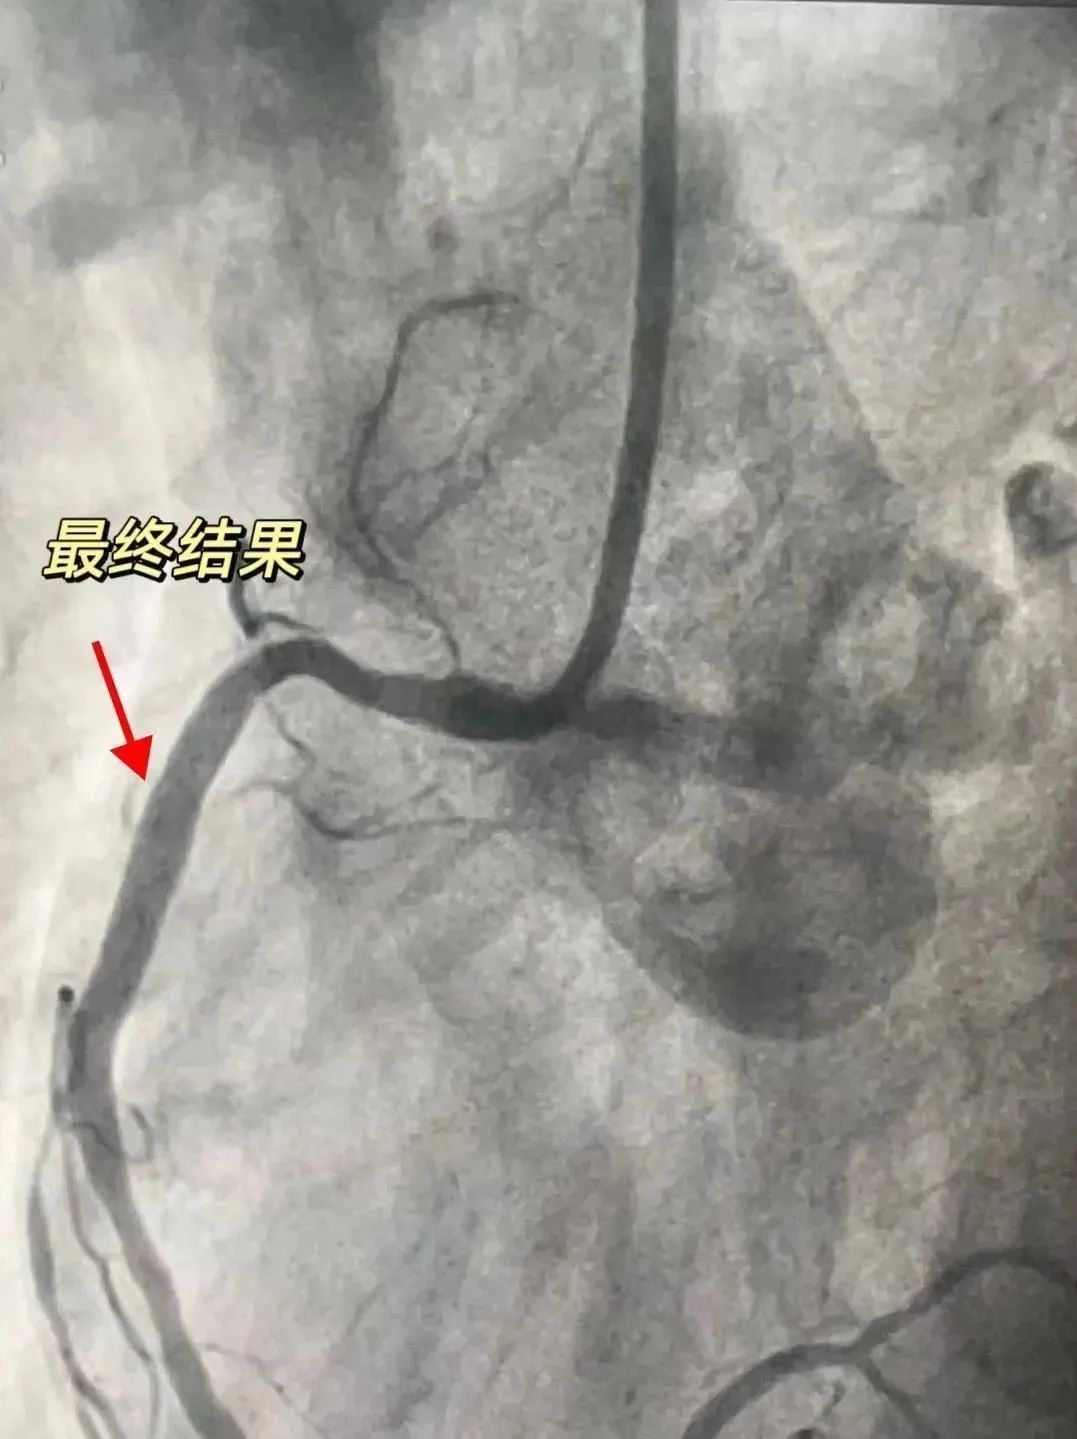

“难点”被击破后,团队顺利为患者植入支架一枚,复查造影及IVUS提示新植入的支架扩张充分,贴壁良好。术后,患者即刻表示胸闷、胸痛症状均得到缓解。